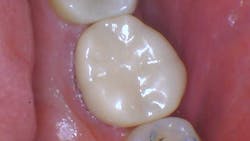

Figure 10: Final prep ready to pull the #2 and scan

Figure 11: Scan of the prep in Primescan